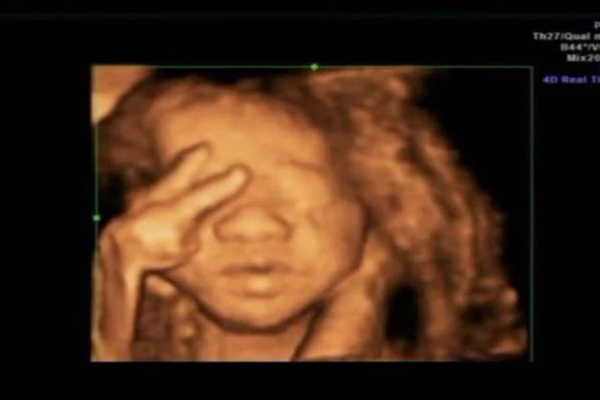

人们都知道,正常婴儿在出生时一定会哭,可一说起胎儿在妈妈肚子里会哭,就会觉得十分新鲜。实际上,据英国《卫报》报道,科学家首次使用4D超声波成像系统时发现,婴儿在出生前数周就已经会大哭不已了。

研究专家认为,婴儿啼哭大多发生在妊娠末期或临产之前。他们可能在还没有出现在分娩室前,就已经在子宮里哭过第一次了。